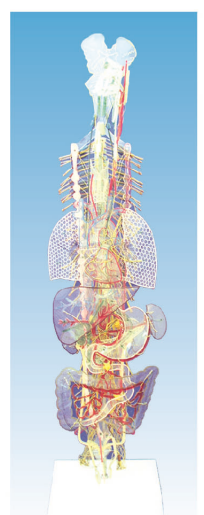

<型号>:SMD124 <模型尺寸>: 300*320*1130(mm) <底座尺寸>: <包装尺寸>: <重量>: <价 格>:询价 <品 牌>:回春 <参数特点>:人体的轴和面模型主要包括:垂直轴、矢状轴、冠状轴;矢状面、冠状面、水平面。

人体的轴和面模型在解剖学中起着至关重要的作用,帮助我们理解人体的结构和运动机制。人体解剖学是研究人体内部结构及其相互关系的科学。它涉及到人体的各个组织、器官、系统的结构、位置和功能等方面的知识。在人体解剖学中,轴与面是非常重要的概念和工具,它们被广泛应用于解剖学的教学、临床诊断和手术操作等领域。

●SMD124:植物性神经立体模型(附总论)